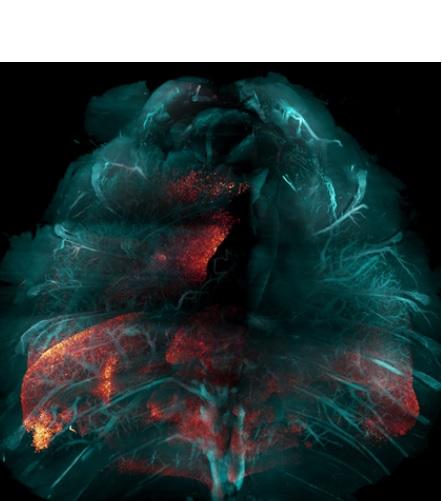

Cette nouvelle technique d’une équipe du Scripps Research (La Jolla) qui permet de rendre les tissus humains (et animaux) transparents, va faciliter considérablement l’étude de nombreuses maladies, à l'échelle du corps et telles que l'infection COVID-19. La méthode, présentée dans la revue Nature Methods, consiste à « nettoyer » les tissus afin de rendre transparents de grands échantillons biologiques. La technique permet ainsi aux scientifiques de visualiser et d'étudier plus facilement les processus biologiques sous-jacents de multiples systèmes et organes, sains ou malades.

Cette nouvelle technique, nommée « Hybrid » combine des éléments de 2 approches existantes de nettoyage des tissus, avec l’objectif de pouvoir étudier de grands échantillons. L’auteur principal, Li Ye, professeur de neurosciences au Scripps Research ajoute que la méthode permet l’étude de « grands systèmes du corps ou même d'animaux entiers ».

Le nettoyage des tissus implique l'utilisation de solvants pour éliminer les molécules qui rendent les tissus opaques (comme la graisse). L’objectif est de rendre les tissus optiquement transparents, tout en maintenant en place et en préservant la plupart des protéines et des structures. Les scientifiques utilisent couramment des balises fluorescentes codées génétiquement ou liées à des anticorps pour marquer des gènes actifs ou d'autres molécules d'intérêt chez un animal modèle de laboratoire, et les balises peuvent ensuite être « imagées » en une seule fois pour l'ensemble de l'animal.

La nouvelle méthode utilise une combinaison séquentielle de solvants organiques et de détergents à base d'eau ainsi que des hydrogels qui permettent de protéger les molécules du tissu qui doivent être préservées. La procédure est simplifiée : « Dans de nombreux cas, il est possible de mettre le tout dans un bocal et le conserver dans un shaker sur votre paillasse jusqu'à l’analyse », explique Victoria Nudell, co-auteur et chercheur au Scrpps. « Il devient possible d’effectuer l’analyse en routine ».

Preuve de concept et application au COVID-19 : La preuve de concept est ici apportée avec toute une série d’expériences, dont la capture, pour la première fois des cellules infectées par le SRAS-CoV-2 dans l'ensemble des poumons d’une souris. Les chercheurs travaillent également au traçage des voies nerveuses dans tout le corps.